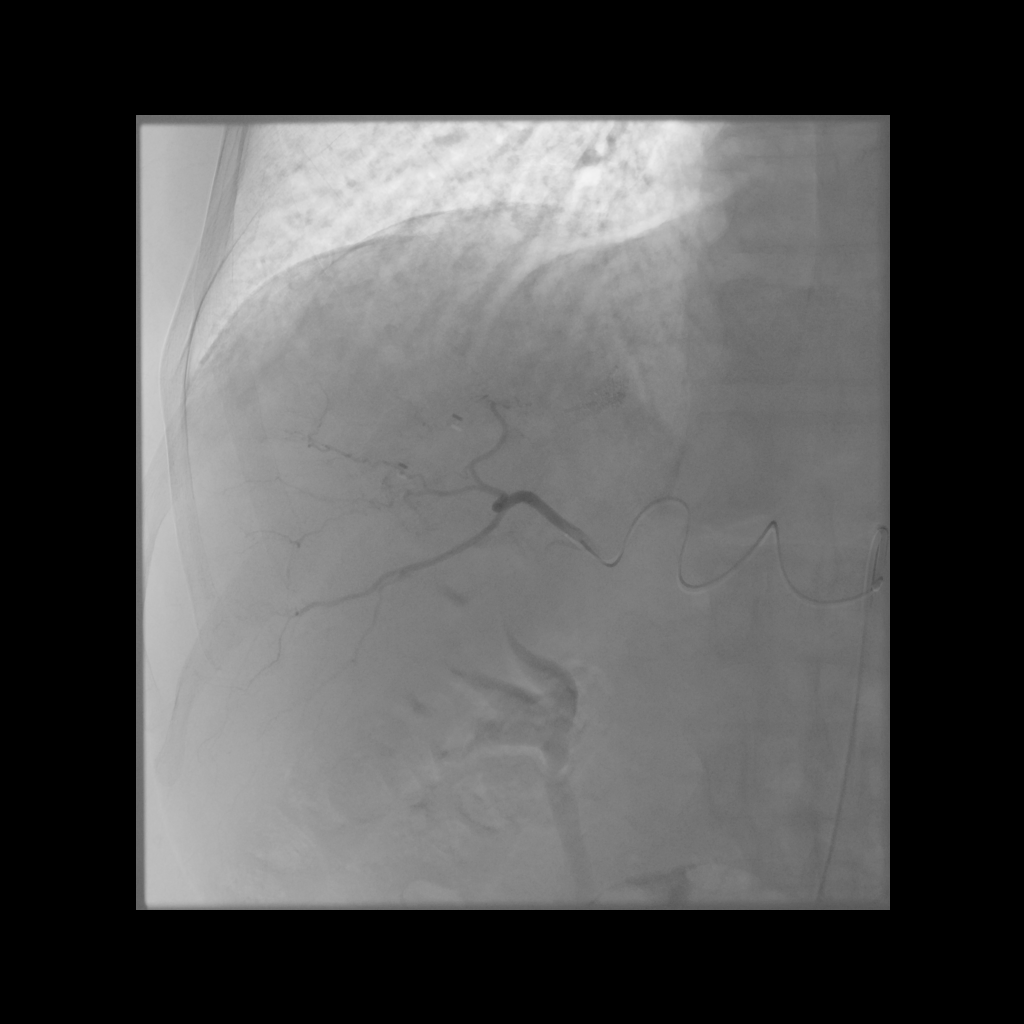

Mapping Angiogram

Comprehensive vascular mapping with CBCT to identify tumor supply and prevent extrahepatic deposition.

• Selective catherization

• Identify variant hepatic arterial anatomy

• Coil embolization of gastroduodenal or right gastric artery

• MAA injection to estimate lung shunt and dosimetry

Treatment Day

• Selective catheterization

• Deliver microspheres slowly under fluoroscopy

• Post-treatment SPECT or PET imaging